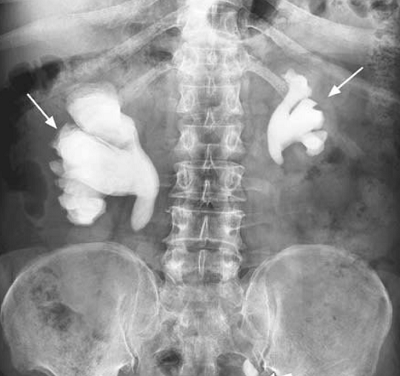

45-year-old woman presents with 2-day history of fever, blood in the urine, and right flank pain. She has a history of recurrent urinary tract infections.

- Picture: Pelvic Radiograph

- Staghorn Sign

- Repeated urinary tract infection with organisms that produce urease produces the staghorn calculi leads to a large formation and growth of the struvite stone in the ureter. This stone is so big that it forms and fills the entire proximal urinary tract, including the branching calyces. This is why the stone appears like horns of a stag.

- Struvite Kidney Stone